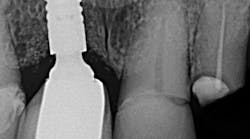

The material you choose to close the screw access chamber with screw-retained implants can be an important factor when considering leakage and bacterial contamination of the dental implant/abutment. Leakage, which can impact the success and longevity of dental implants, has been identified as a major contributing factor to the introduction of bacteria and inflammatory reactions at the implant-abutment connection, leading to problems such as oral malodor, inflammation, and peri-implant bone loss (figure 1).

Peri-implant mucositis and peri-implantitis are the primary diseases affecting dental implant health. Peri-implantitis is a pathological condition occurring in tissues around dental implants, characterized by inflammation in the peri-implant connective tissue and progressive loss of supporting bone.

One of the causes of peri-implantitis can be attributed to microgaps, or inadequate sealing around the implant, that can allow bacteria to infiltrate, leading to inflammation and infection of the peri-implant tissues. If left untreated, peri-implantitis can cause bone loss, implant instability, and, ultimately, implant failure.

Studies have demonstrated that during mastication, fluid can enter microgaps in the implant/abutment space, allowing bacteria and endotoxins to enter.1 This microleakage is an important risk factor for complications such as bone resorption, peri-implant inflammation, and central screw loosening.2